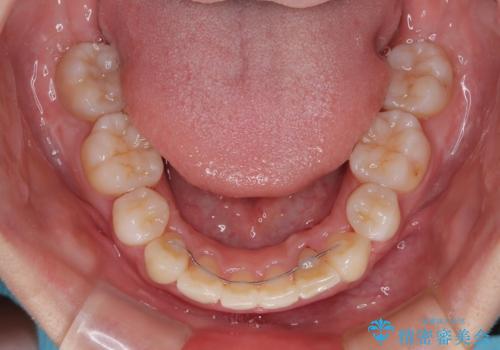

深い咬み合わせの改善に時間がかかりましたが、下顎前歯がしっかりと見えるまでに整えることができ、口元の突出感も大幅に改善することができました。